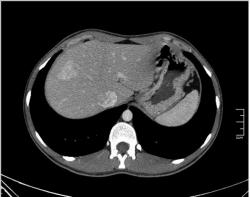

КТ печени. Наблюдения для размышления.

Уважаемые коллеги, особенно врачи КТ. Надеюсь что данная публикация окажется полезной для многих из Вас. Ниже представлены сканы печени; предлагаю Вам ознакомится с ними и высказать свое мнение. Пациент мужчина средних лет, специфичных жалоб не предъявляет.

Уважаемый v1tal! Огромная Вам благодарность; Вы назвали ключевое слово: фаза! Высказанная Вами мысль, это моя основная цель данной публикации. Постараюсь позже более детально объяснить почему. Представленные сканы выше, были выполнены на стандартной портальное фазе. А сейчас, я покажу сканы данного пациента выполненные на артериальной фазе :

Да Ola la, Вы абсолютно правы; это Фокальная Нодулярная Гиперплазия печени (FNH Focal Nodular Hyperplasia). Одна из немногих гиперваскулярных опухолей печени. Наверное некоторые коллеги спросят, и зачем было изначально публиковать портальную фазу, на которой «не видно» (хотя опухоль видна, пусть и не напрямую, и Nela это доказала); и только потом показывать сканы на артериальной фазе, на которой всё «красиво и показательно». Постараюсь объяснить.